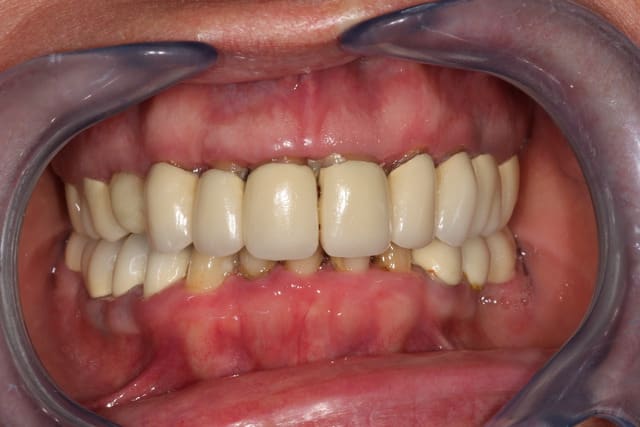

Un gros cas à démarrer: une charmante patiente début cinquantaine, hyper complexée par son sourire, inconfort total, etc...

Tout est à refaire: paro,cérams, quelques implants en vue, bref un boulot sympa à faire.

Ma question concerne les papilles: les céram rectangulaires sont hideuses, mais après la paro, le problème des papilles ne va pas s'arranger et lui faire des couronnes plus féminines va créer des trous noirs...

Je ne me vois pas non plus faire des élongations coronaires vue la position de la ligne du sourire...

le bord libre des incisives est trop bas

le recouvrement me semble assez important

Les incisives sont trop longues

avoir une belle courbe de spe se fera difficilement. La marche d'escalier est inévitable sauf a faire des élongations coronaires partout. A voir la longueur des racines.

Y a un bon problème squelettique quand même, le pré maxillaire équin, ça limite les perspectives.

a part ça, on jurerai qu'elle porte un dentier de farce et attrape. je comprends qu'elle soit complexée.

En plus ce qu'on ne voit pas, c'est que toutes les cérams sont débordantes de presque 2 mm...

Bon, on va faire un wax-up, déposer tout ça, mettre sous provisoire, faire un bon traitement paro, faire des plasties gingivales pour retrouver un semblant de papilles, et ensuite à mon protho de jouer.